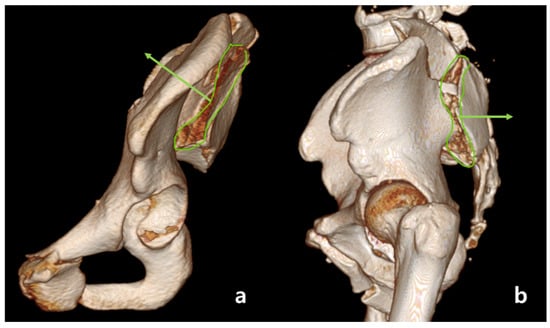

2.2. Definition of Anterior Sacroiliac Fracture Dislocation